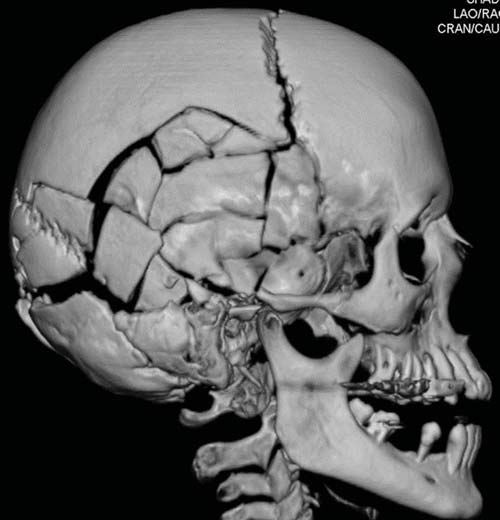

Whereas in cases of sharp trauma the type of inflicting instrument may be discerned in most cases, this is not true for all contusions and lacerations of the scalp. For instance, it is obviously of utmost importance to distinguish between scalp contusions, due either to a fall or to a blow with an instrument. The fracture pattern of the skull and typical cerebral lesions can solve this problem with a large degree of certainty. If the head strikes a broad, flat surface, such as the ground, the skull is flattened at the point of impact. Due to this resulting inward bending, distant areas of the skull are bent outward. Fractures do not begin at the point of impact but at the point of outbending at the external surface [10,11]. For instance, a fall with a low-energy impact to the occipital skull will therefore classically lead to linear fractures (Figure D3.2.10). If the impact of the large, flat surface is great enough, complete or incomplete circular fractures may arise around the impact point at the edge of inward and outward bending. With an even greater amount of energy, the severe inbending at the point of impact leads to stellate fractures arising from the impact center. A combination of circular and stellate fracture lines creates a distinct spider web-like fracture system. Later fracture lines will not cross preexisting fracture lines, as the necessary tension is lacking in previously fractured areas. This phenomenon, also known as the "Puppe-rule" can help assess the timing of skull injuries when more than one impact point is seen.

If the impact occurs with high energy and a small surface area, i.e., in blows with hammers, the result is a small, depressed skull fracture (Figure D3.2.11 and Figure D3.2.12). Here, the brain is generally only affected in the immediate vicinity of the impact. A blow to the head (i.e., the occiput) will therefore mainly result in a cerebral injury to the occipital brain regions. Several blows to the head can obscure the small, depressed fracture due to the severe destruction of the concerned skull region. By contrast, a fall from great height or from an upright position onto the ground will lead to a completely different fracture pattern and cerebral injury (Figure D3.2.13). Here, linear or, if the energy involved is great enough, circular fractures are commonly encountered. Simple linear fractures are, however, also seen in (lowenergy) blows to the head. In these cases, the plain radiograph of the skull does not suffice to distinguish between a blow and a fall. Here, postmortem MSCT imaging can deliver quick and reliable results. By enabling the visualization of the brain, coup-contrecoup lesions can be detected. This constellation of impact-near and impact-far injuries is often seen in falls. They are an absolute rarity in cases of homicidal blows to the head. Thus, by visualization of the brain, the pathologist may be able to discern between a blow and a fall even if the external wound morphology may be obliterated or hidden (e.g., due to secondary animal involvement such as ants). The cerebral injuries inflicted by blows and falls are discussed in detail in Chapter D3.3.